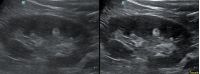

Ультразвуковая волна распространяется от пьезокристалла в направлении плоскости сканирования. Если волна отражается от поверхности исследуемой структуры под прямым углом и возвращается к пьезокристаллу напрямую, на сонограмме появляется четкая дифференцировка структуры и подчеркнутые контуры. Прямое отражение - самый важный критерий техники сканирования для измерения точных размеров органа. В случае отражения волны не под прямым углом эхогенность структуры меняется, дифференцировка на слои падает, контуры становятся нечеткими. Таким образом косой срез дает огромную погрешность измерения и затрудняет описание эхоструктуры объекта.

Как достичь прямого отражения Достаточно расположить объект на экране горизонтально, с помощью наклона датчика, чтобы волна отражалась от поверхности под прямым углом. При любом типе исследования любого органа или системы прямое отражение – залог достоверных результатов.